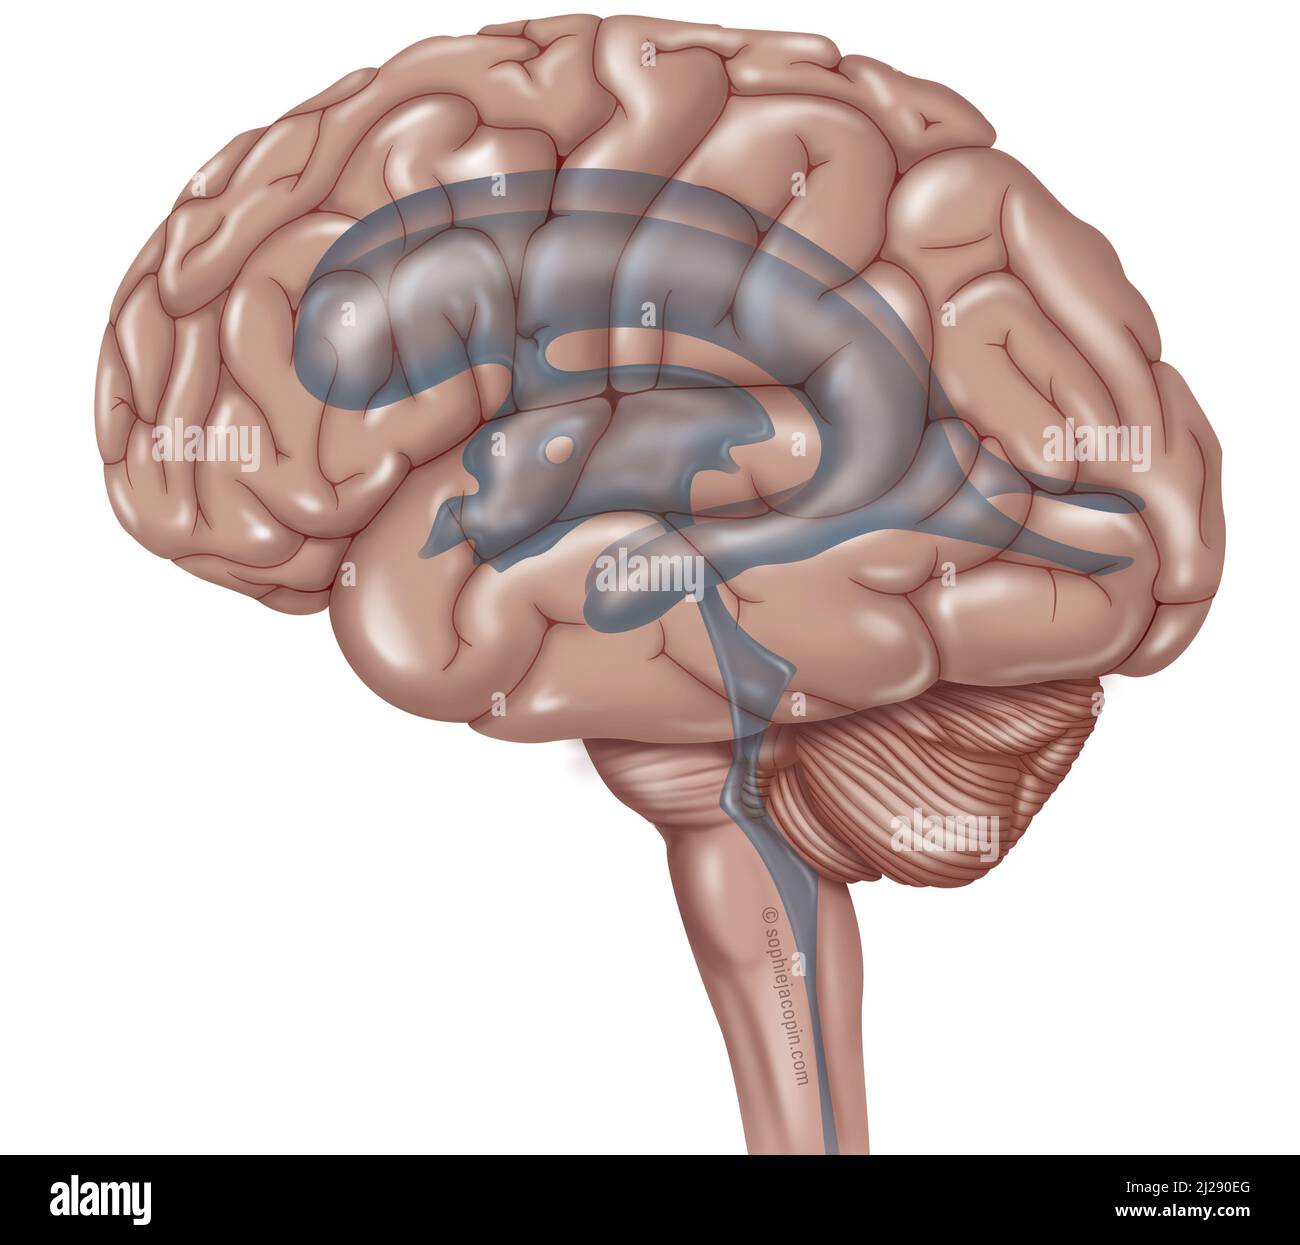

RF2T7NGWH–Ventrikel und zerebrales Aquädukt laterale Röntgenansicht 3D-Rendering-Illustration. Menschliches Gehirn und Ventrikelsystem Anatomie, Medizin, Gesundheitswesen, Scienc

RFPXA6XR–Der zerebrospinalen Flüssigkeit (CSF) ist das Gehirn und das Rückenmark von Auswirkungen schützt, eliminiert Abfälle aus dem Gehirn und Rückenmark, und hilft Giftstoffe im